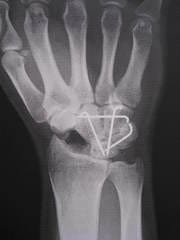

本日、ドクターにお願いしてオペ直前のレントゲンをゲットしましたので

お見せいたします。

1枚目オペ前日 2枚目オペ直後 3枚目昨日 いかがですか?

骨の写真ばっかりですみません(汗)